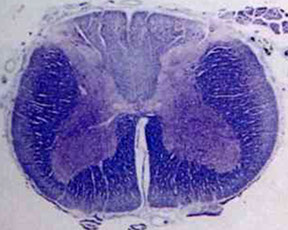

Poliomyelitis

- Following ingestion, this enterovirus replicates in lymphoid tissue of the intestine, leading to viremia

- Invades the CNS bringing about selective destruction of lower motor neurons ("neuronophagia"), especially anterior horn cells, resulting in profound weakness